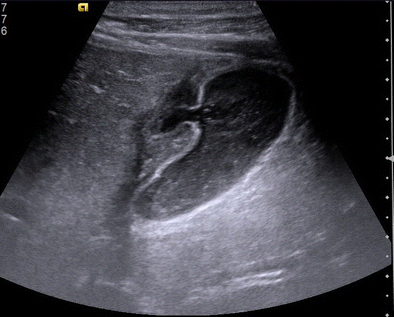

Fig. 2

Shows the walled off pericholecystic collection with internal septations